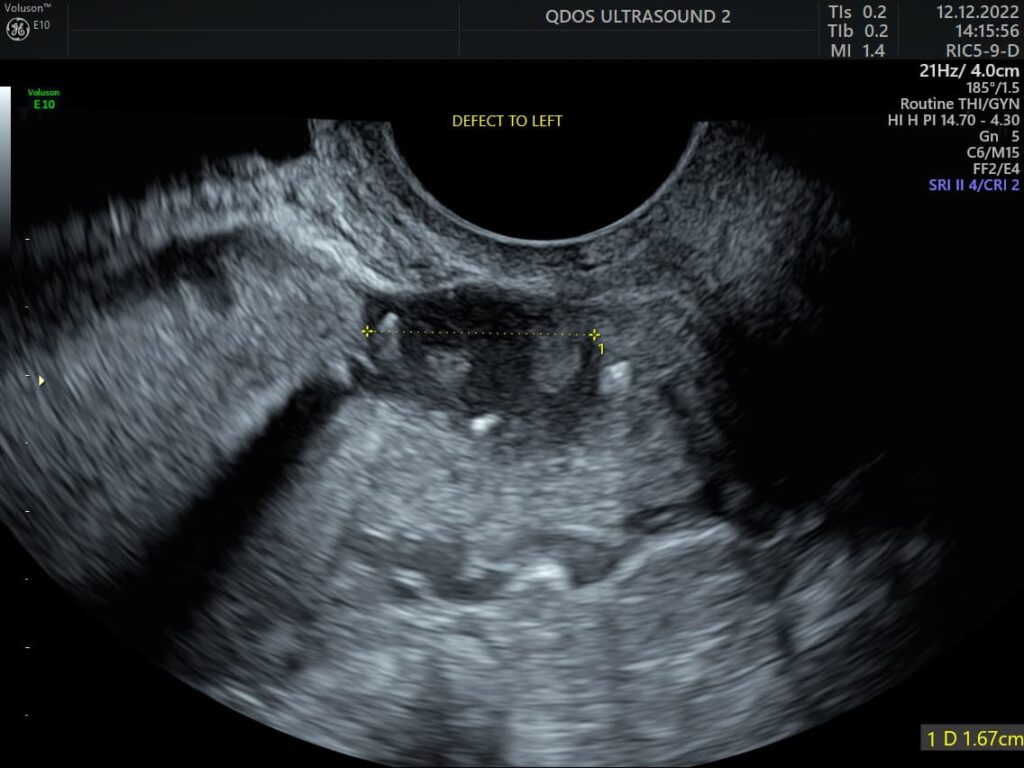

Abnormal bleeding sometimes can be linked to several conditions visible on an ultrasound, such as polyps, fibroids, abnormal thickening of the uterus lining, or unusual ovarian activity. At QDOS Ultrasound, we specialise in detailed gynaecological imaging to recognise the difference between these abnormal findings, as well as to recognise variations of normal.

Painful or heavy periods are common reasons for a gynaecology ultrasound. Conditions like fibroids, endometriosis, adenomyosis, uterine polyps, or abnormal thickening of the uterus lining may be responsible. Whilst endometriosis cannot be excluded by ultrasound, our team are specialists in looking for the recognisable ultrasound features of endometriosis.